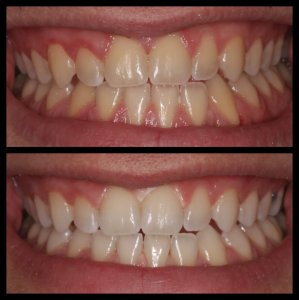

ΛΕΥΚΑΝΣΗ ΔΟΝΤΙΩΝ